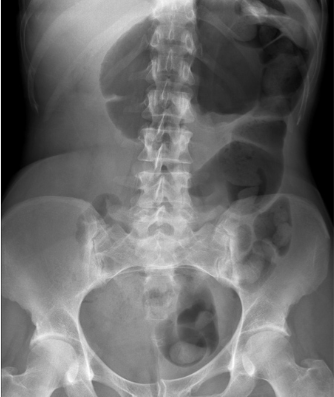

UC: Toxic megacolon

• Large bowel obstruction; loss of haustra